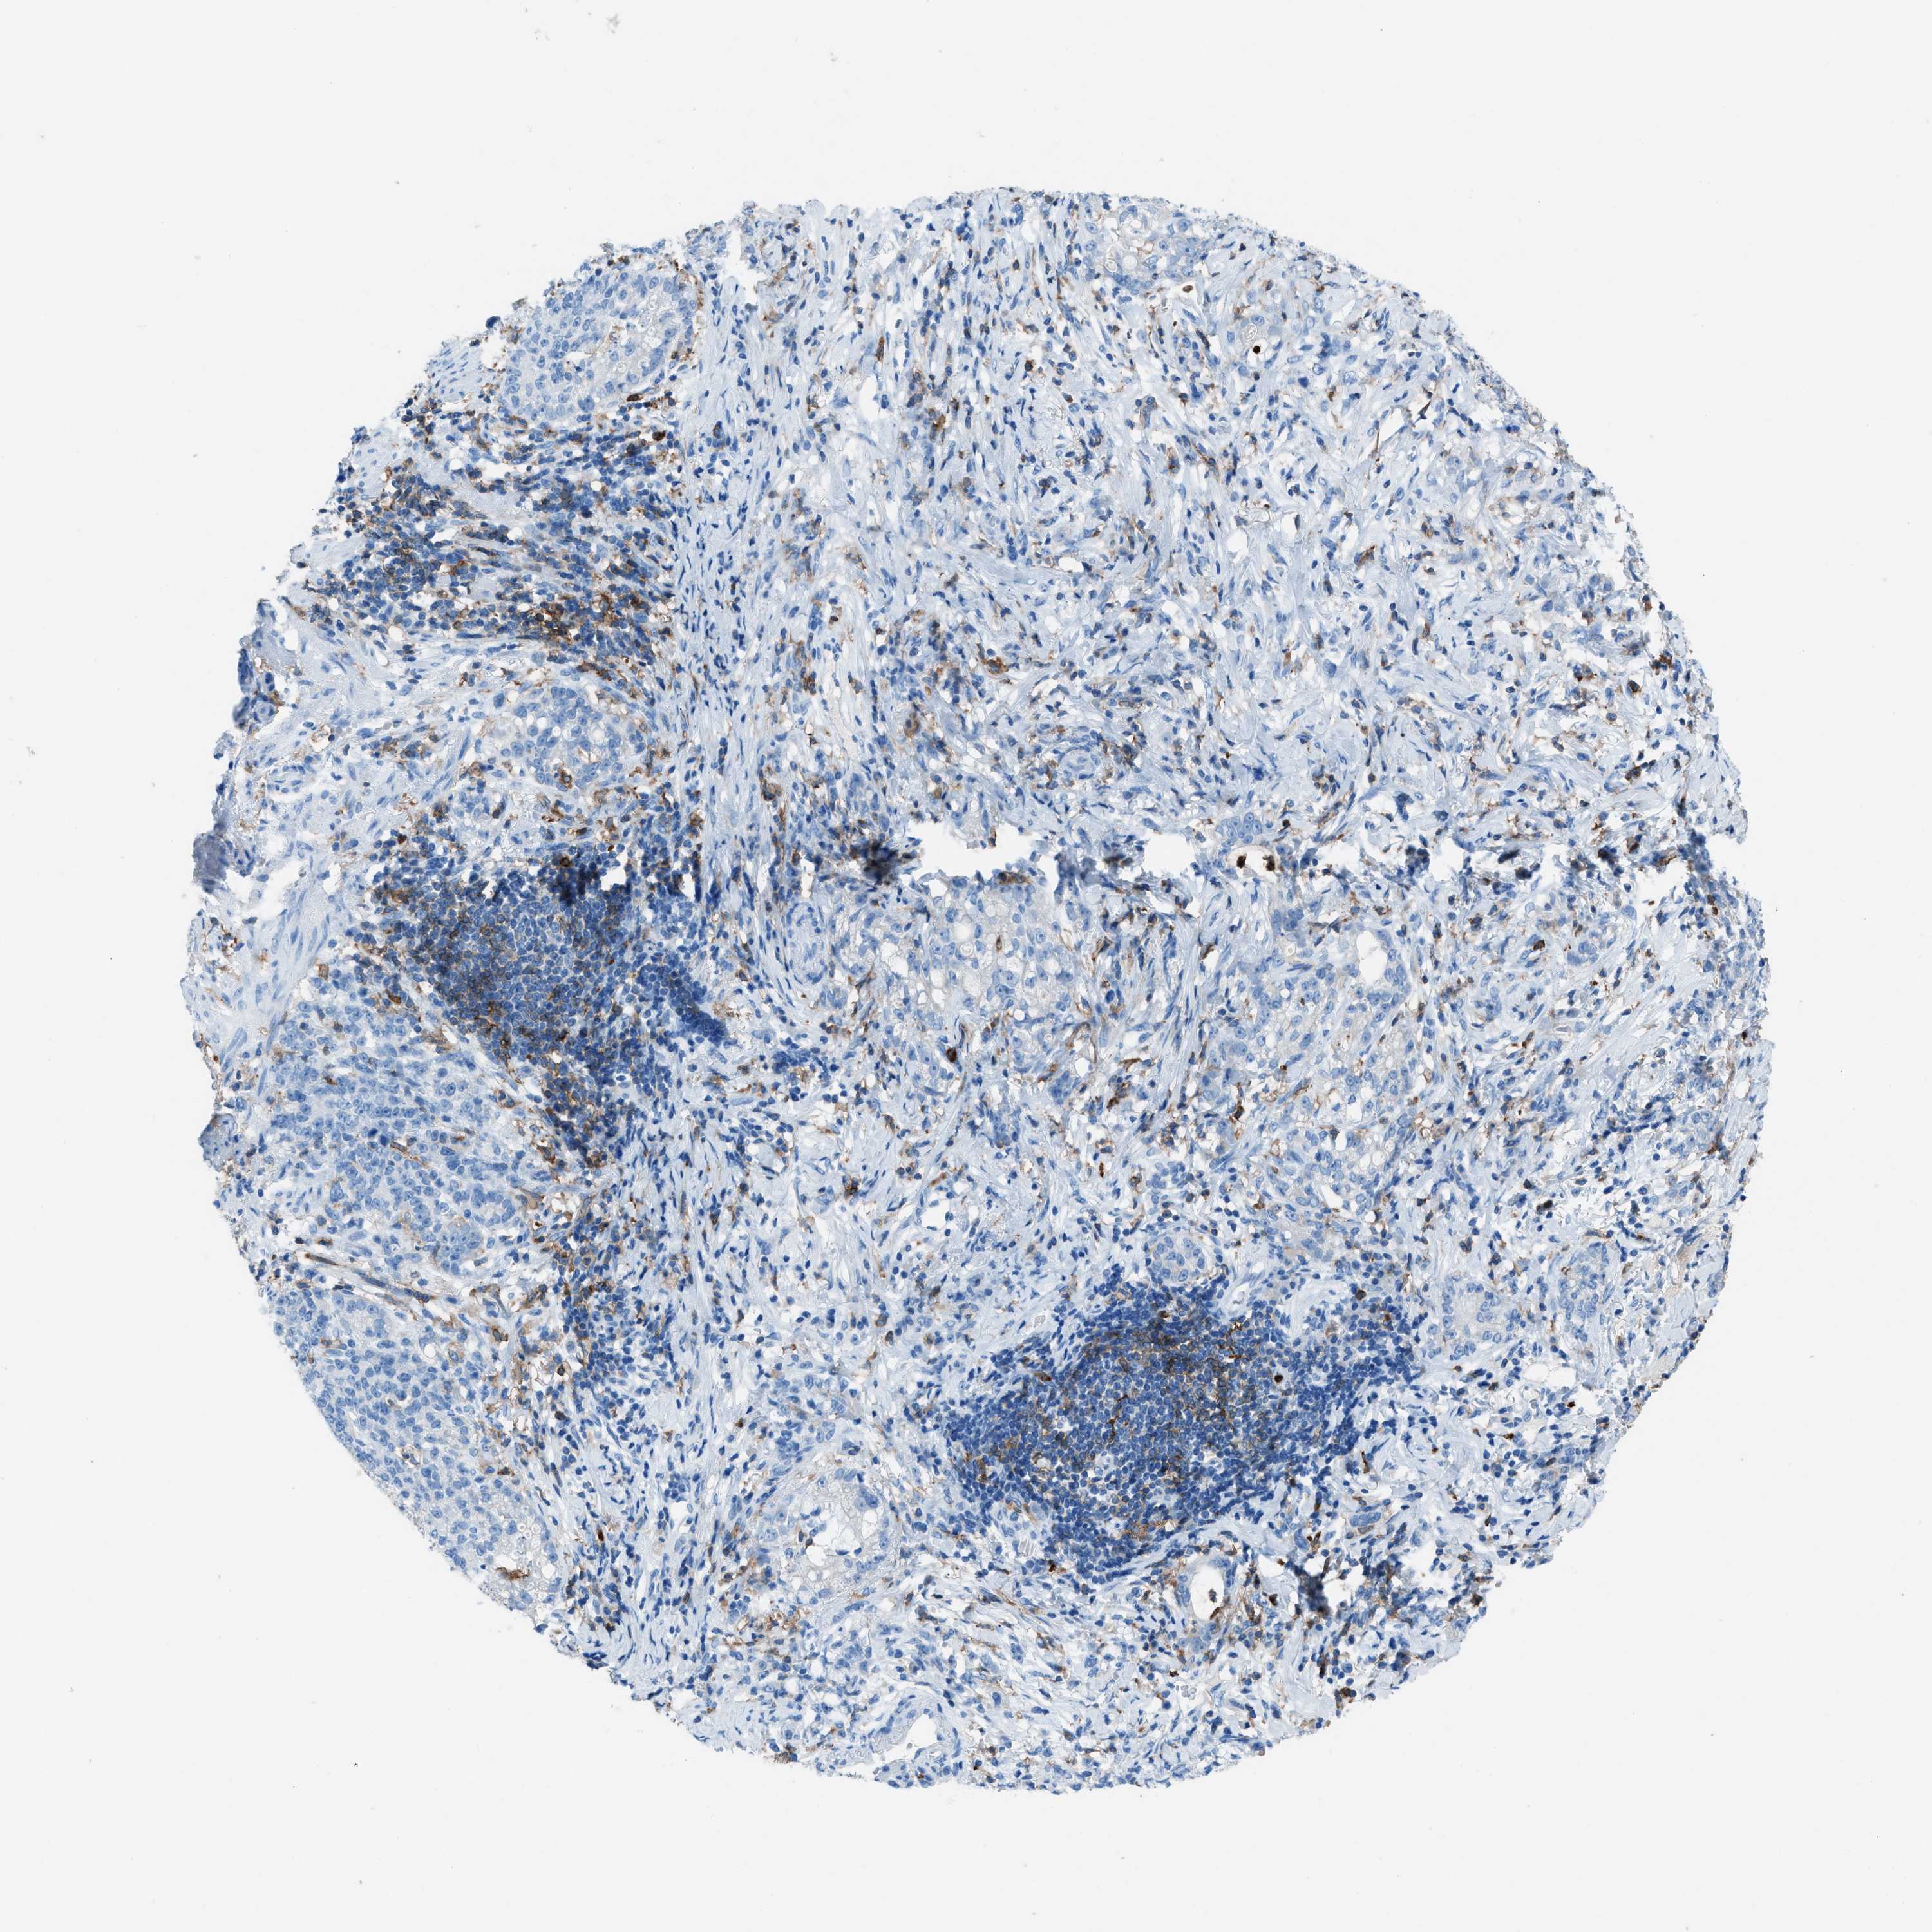

STOMACH CANCER - Protein expressioni

A mouse-over function shows sample information and annotation data. Click on an image to view it in a full screen mode. Samples can be filtered based on level of antibody staining by selecting one or several of the following categories: high, medium, low and not detected. The assay and annotation is described here.

Note that samples used for immunohistochemistry by the Human Protein Atlas do not correspond to samples in the TCGA dataset.

Antibody stainingi

Antibody staining in the annotated cell types in the current human tissue is reported as not detected, low, medium, or high, based on conventional immunohistochemistry profiling in selected tissues. This score is based on the combination of the staining intensity and fraction of stained cells.

Each image is clickable and will lead to virtual microscopy that enables deeper exploration of all samples and also displays staining intensity scores, fraction scores and subcellular localization as well as patient and tissue information for each sample.

Antibody HPA008877

Antibody HPA016894

Staining

High

Medium

Low

Not detected

Intensity

Strong

Moderate

Weak

Negative

Quantity

>75%

75%-25%

<25%

None

Location

Nuclear

Cytoplasmic/membranous

Cytoplasmic/membranous,nuclear

Adenocarcinoma, NOS